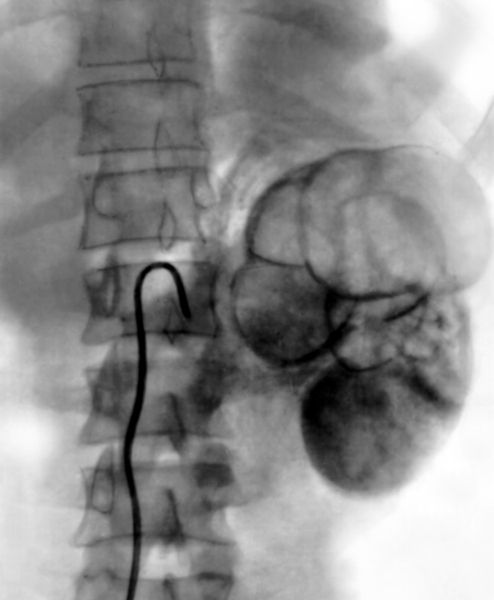

Понимание кавернозного туберкулеза почки

Раздел: Мудрость в деталях